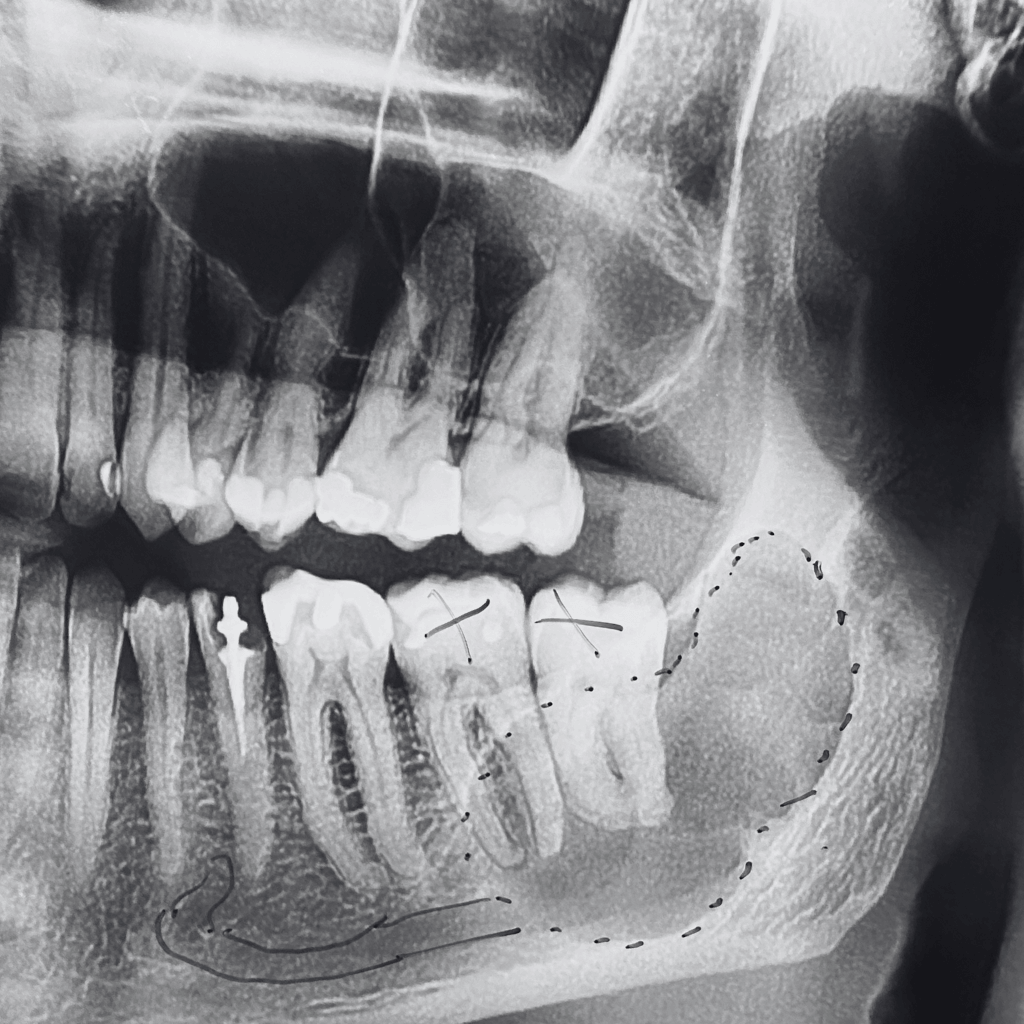

Биопсия и планиране

При необходимост се извършва биопсия за уточняване на диагнозата или се планира хирургично отстраняване на формацията, в зависимост от клиничния случай.

Хирургично отстраняване

Интервенцията се извършва под локална или обща анестезия, в зависимост от големината, разположението и индивидуалните особености на случая.

Отстранената тъкан се изпраща за анализ в специализирана лаборатория.